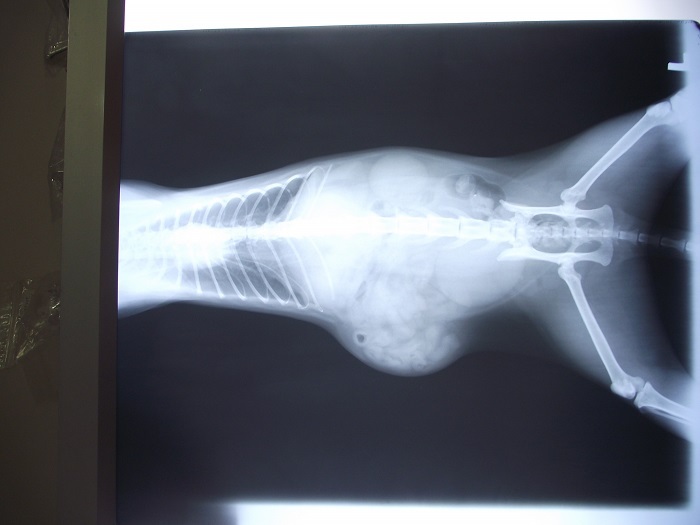

主題: 肚子側邊凸出,肌肉撕裂傷導致器官移位 申請者姓名: 簡嘉 花色: 申請日期: 2013-05-11 07:36:50 申請者部落格: 申請者臉書網址: 所在縣市/合作醫院: 台北市/康廷動物醫院 治療費用: 14600元 需求人數: 16人 已結案 (2013-06-27 14:38:04) 報名人員: 咪咪(已付款)、Emily Chou x10(已付款)、草堂墨客(已付款)、KK(已付款)、姚怪賢(已付款)、Becca Huang(已付款)、Melody Wu(已付款)、 候補人員: 動物病情說明: 白白是生活在街貓多且校園不歡迎的地方,所以餵養人拜託志工幫忙誘捕街貓們結紮..

在捕到送醫X光檢查後:

原來白白曾經遭受到不明原因撞擊而導致肌肉撕裂傷..並且導致腸子腎臟器官都移位了

撕裂傷的腫大處,有10幾公分大小,手術不易處理,必須進一步採取人工網膜把受傷的洞洞補起來..